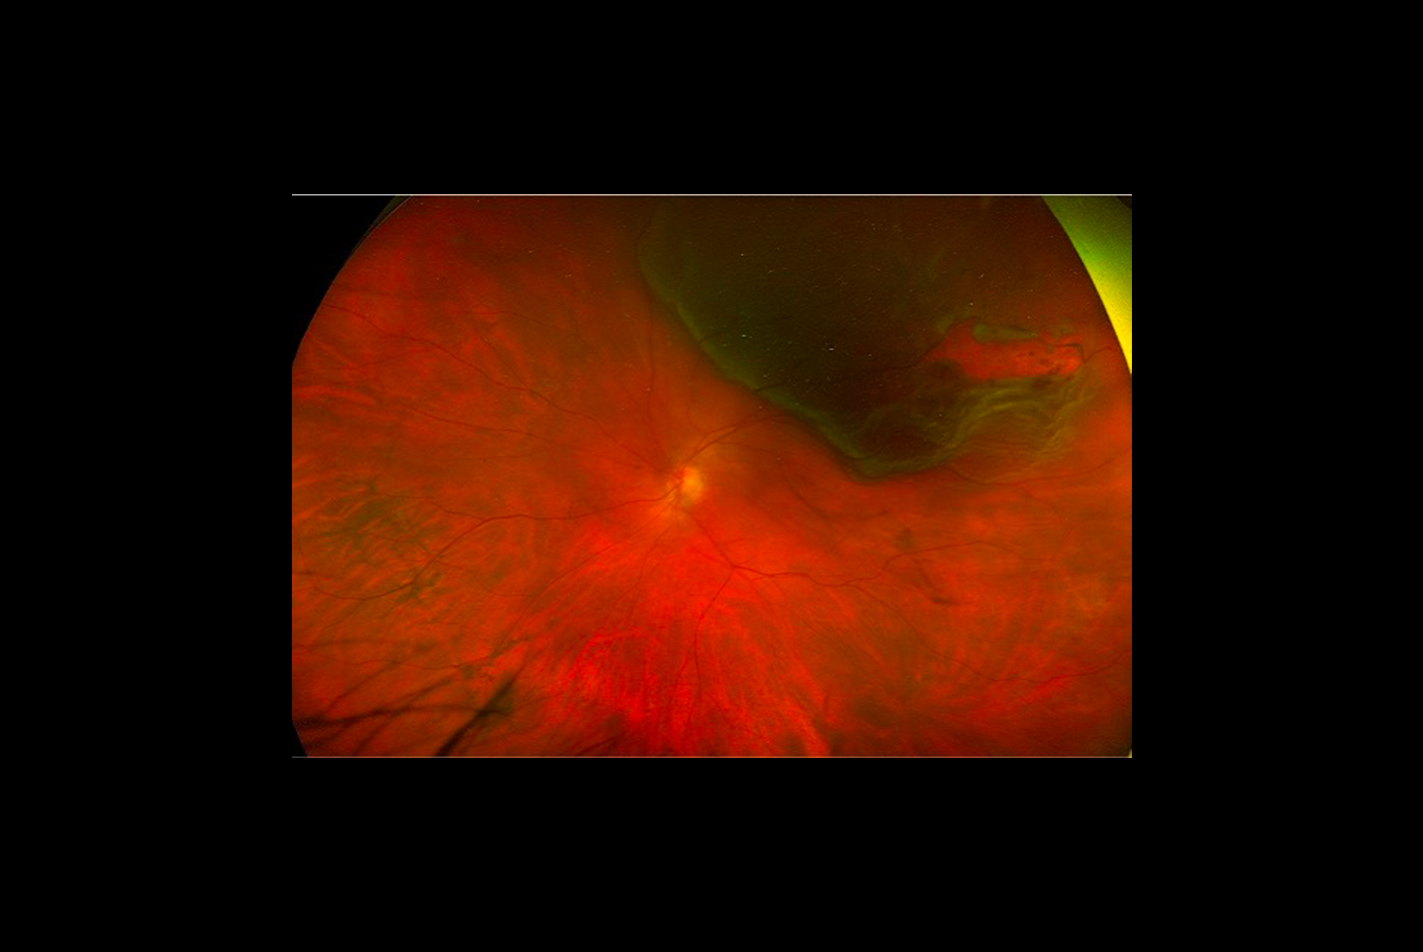

ophtavalmy.frFond D’oeil_Décollement Rétine Supérieur Avec Déchirure Rétinienne

ophtavalmy.frFond D’oeil_Décollement Rétine Supérieur Avec Déchirure Rétinienne

www.pourlavision.orgDécollement De La Rétine (DR) - Rétine Sud

www.pourlavision.orgDécollement De La Rétine (DR) - Rétine Sud